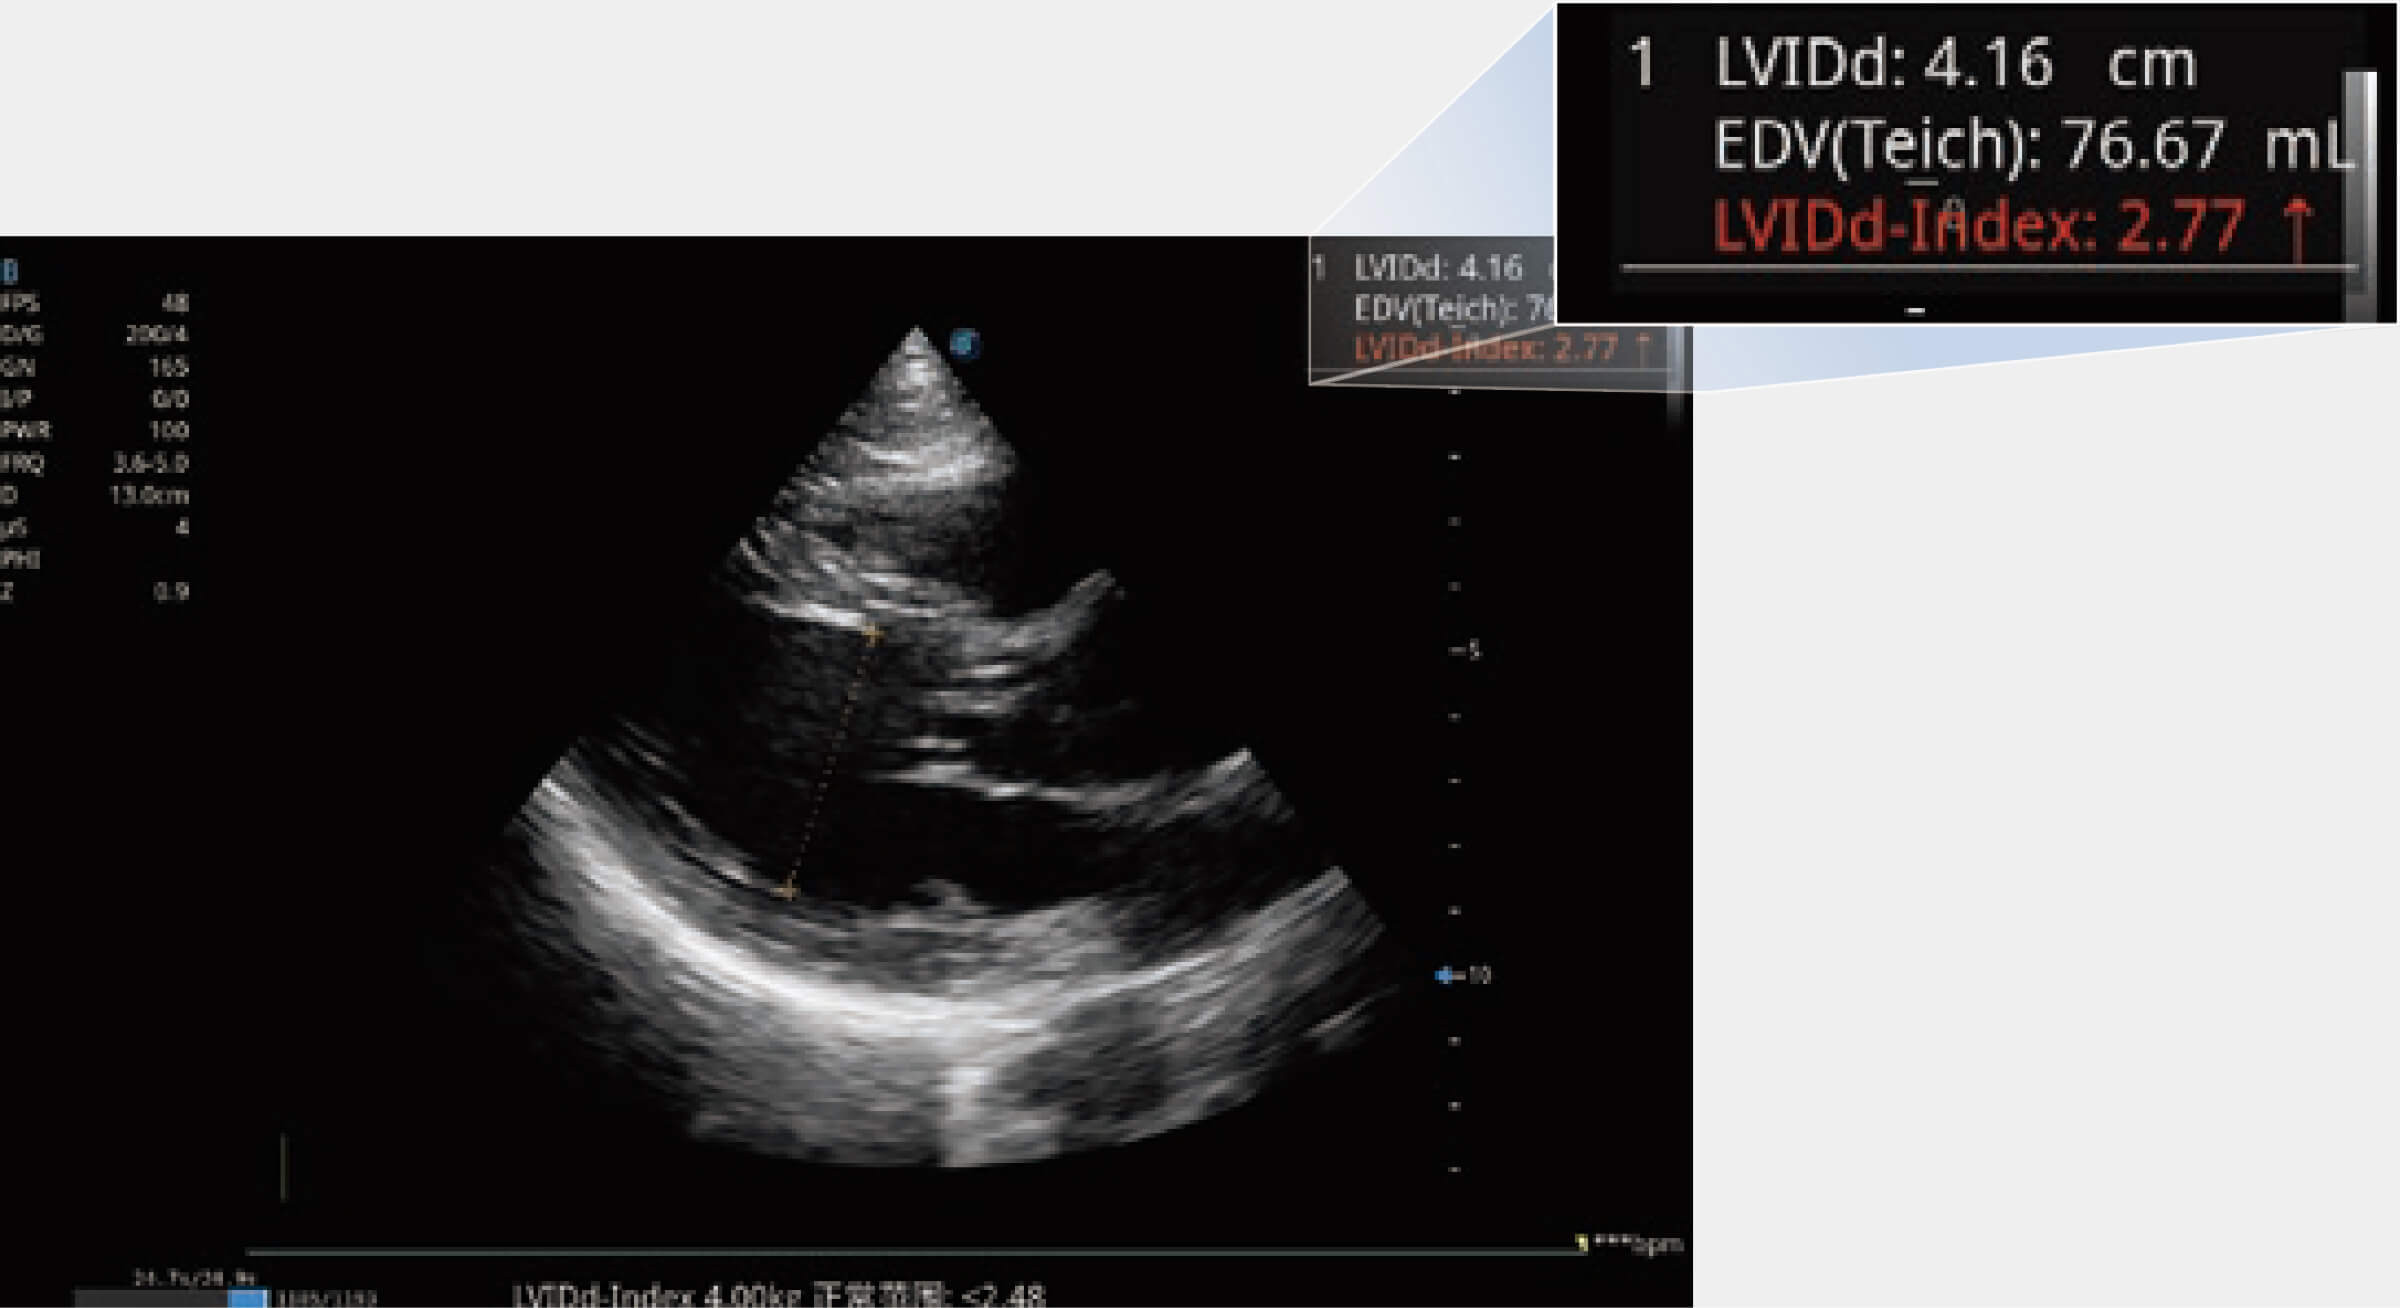

ProPet 80 配備了豐富的心臟探頭群、先進(jìn)的成像技術(shù)和專業(yè)的心臟測量工具,可幫助動物醫(yī)生為不同體型和生理結(jié)構(gòu)的動物提供心臟和心肌功能的全面評估。

當(dāng)心臟測量結(jié)果超出正常范圍時,可實(shí)時預(yù)警提示動物醫(yī)生,減少疾病漏診概率。